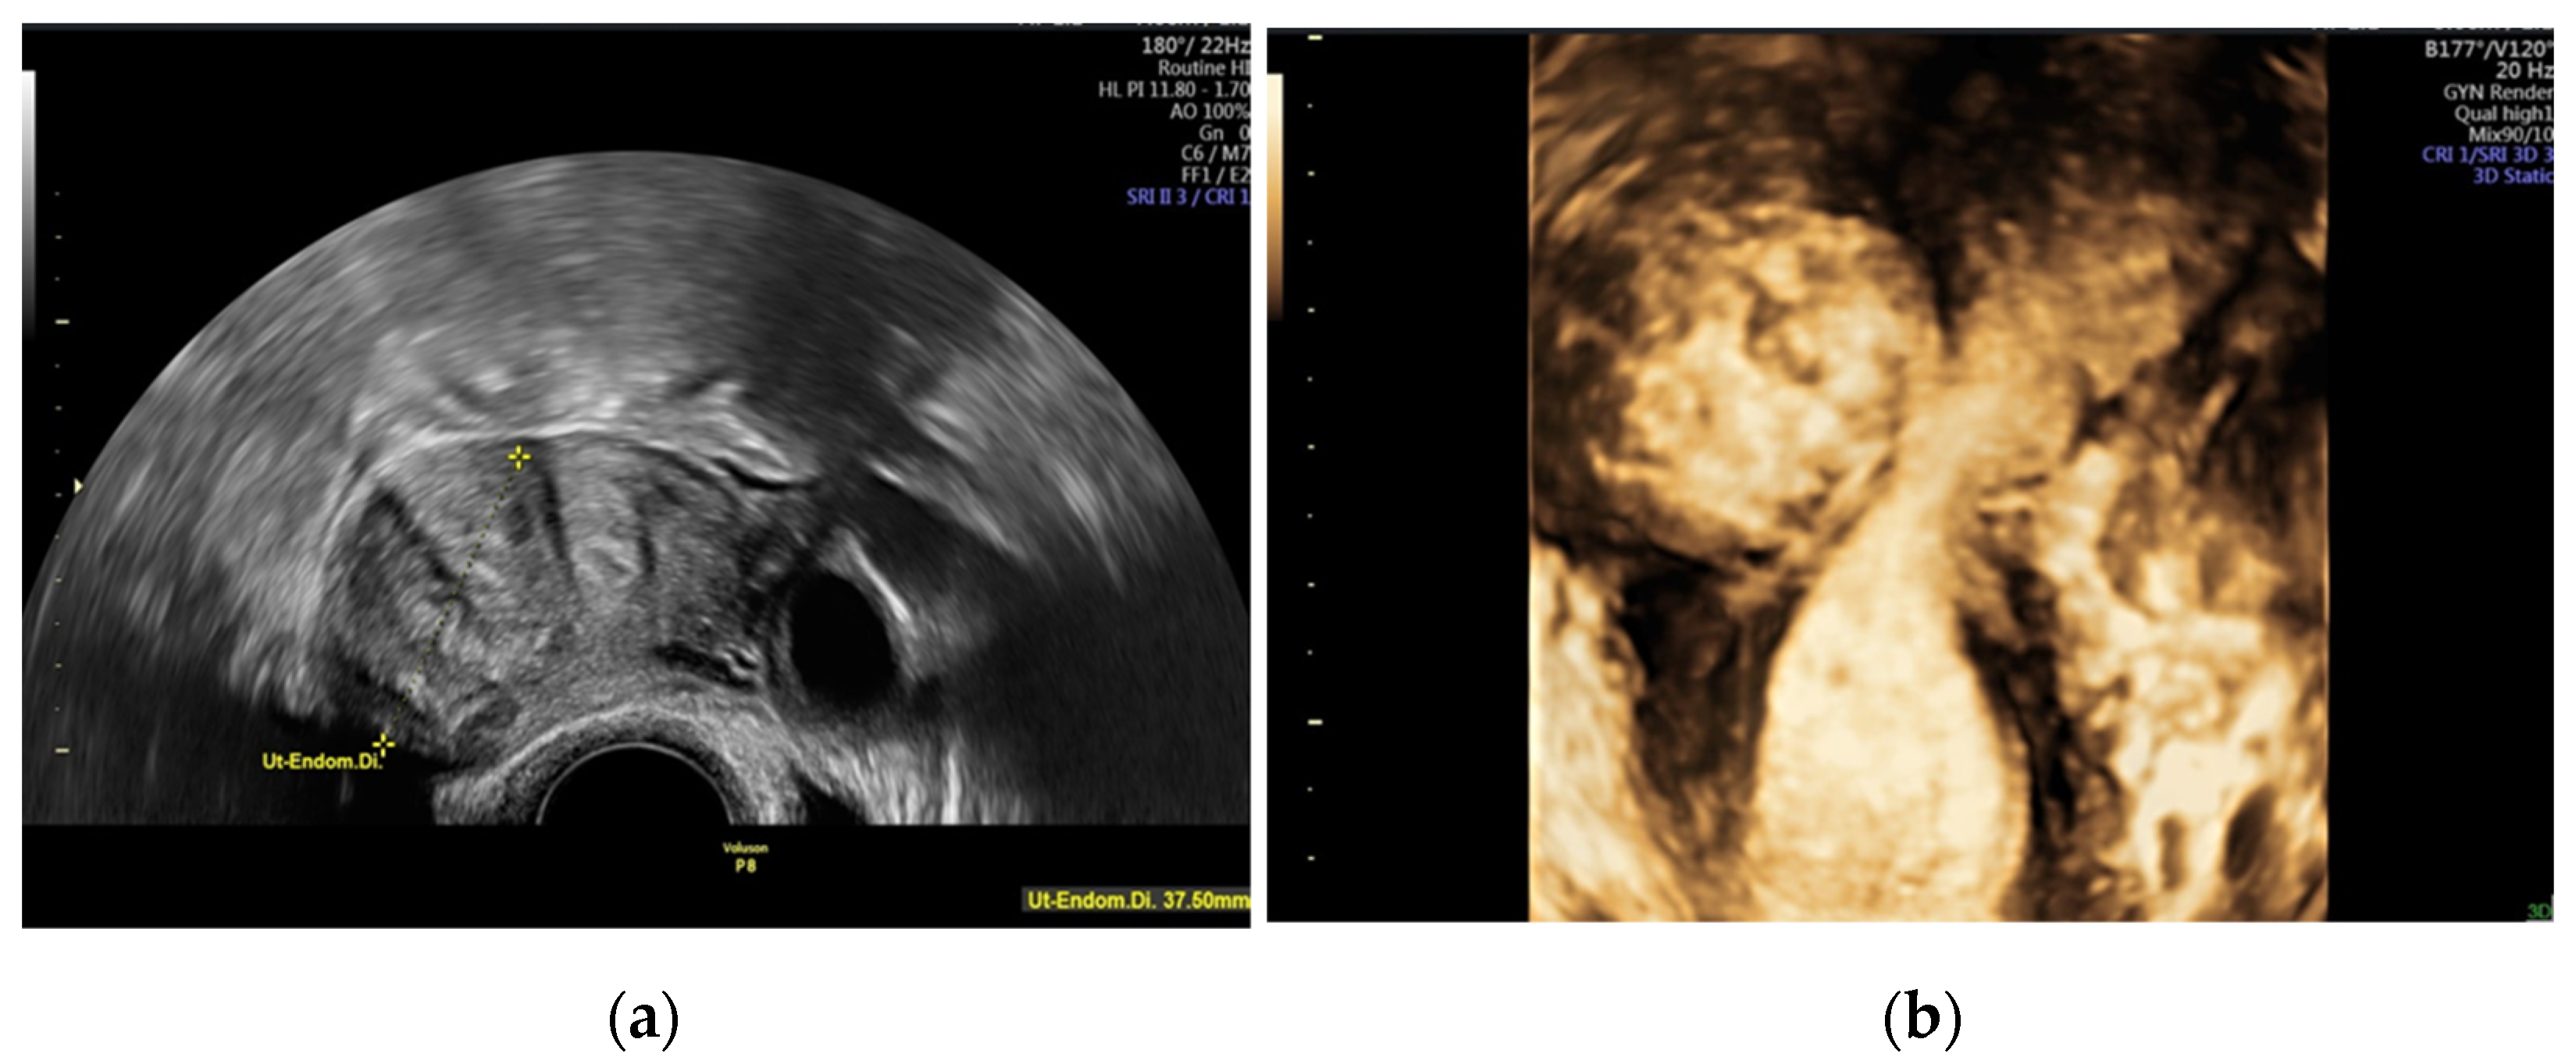

- Andreotti, R.F.; Fleischer, A.C. Practical applications of 3D sonography in gynecologic imaging. Radiol. Clin. N. Am. 2014, 52, 1201–1213. [Google Scholar] [CrossRef]

- Wong, L.; White, N.; Ramkrishna, J.; Araujo Júnior, E.; Meagher, S.; Costa Fda, S. Three-dimensional imaging of the uterus: The value of the coronal plane. World J. Radiol. 2015, 7, 484–493. [Google Scholar] [CrossRef]

- Van den Bosch, T.; Dueholm, M.; Leone, F.P.; Valentin, L.; Rasmussen, C.K.; Votino, A.; Van Schoubroeck, D.; Landolfo, C.; Installé, A.J.; Guerriero, S.; et al. Terms, definitions and measurements to describe sonographic features of myometrium and uterine masses: A consensus opinion from the Morphological Uterus Sonographic Assessment (MUSA) group. Ultrasound Obstet. Gynecol. 2015, 46, 284–298. [Google Scholar] [CrossRef]